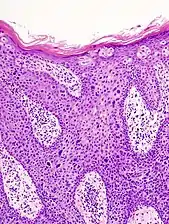

Histopathologically, the epidermis in cSCC in situ (Bowen's disease) will show hyperkeratosis and parakeratosis. There will also be marked acanthosis with elongation and thickening of the rete ridges. These changes will overly keratinocytic cells which are often highly atypical and may in fact have a more unusual appearance than invasive cSCC. The atypia spans the full thickness of the epidermis, with the keratinocytes demonstrating intense mitotic activity, pleomorphism, and greatly enlarged nuclei. They will also show a loss of maturity and polarity, giving the epidermis a disordered or "windblown" appearance.

Two types of multinucleated cells may be seen: the first will present as a multinucleated giant cell, and the second will appear as a dyskeratotic cell engulfed in the cytoplasm of a keratinocyte. Occasionally, cells of the upper epidermis will undergo vacuolization, demonstrating an abundant and strongly eosinophilic cytoplasm. There may be a mild to moderate lymphohistiocytic infiltrate detected in the upper dermis.[12]

Histopathology of squamous-cell carcinoma in situ (black arrow), compared to normal skin, showing marked atypia.

Squamous-cell carcinoma in situ, showing prominent dyskeratosis and aberrant mitoses at all levels of the epidermis, along with marked parakeratosis.[12]